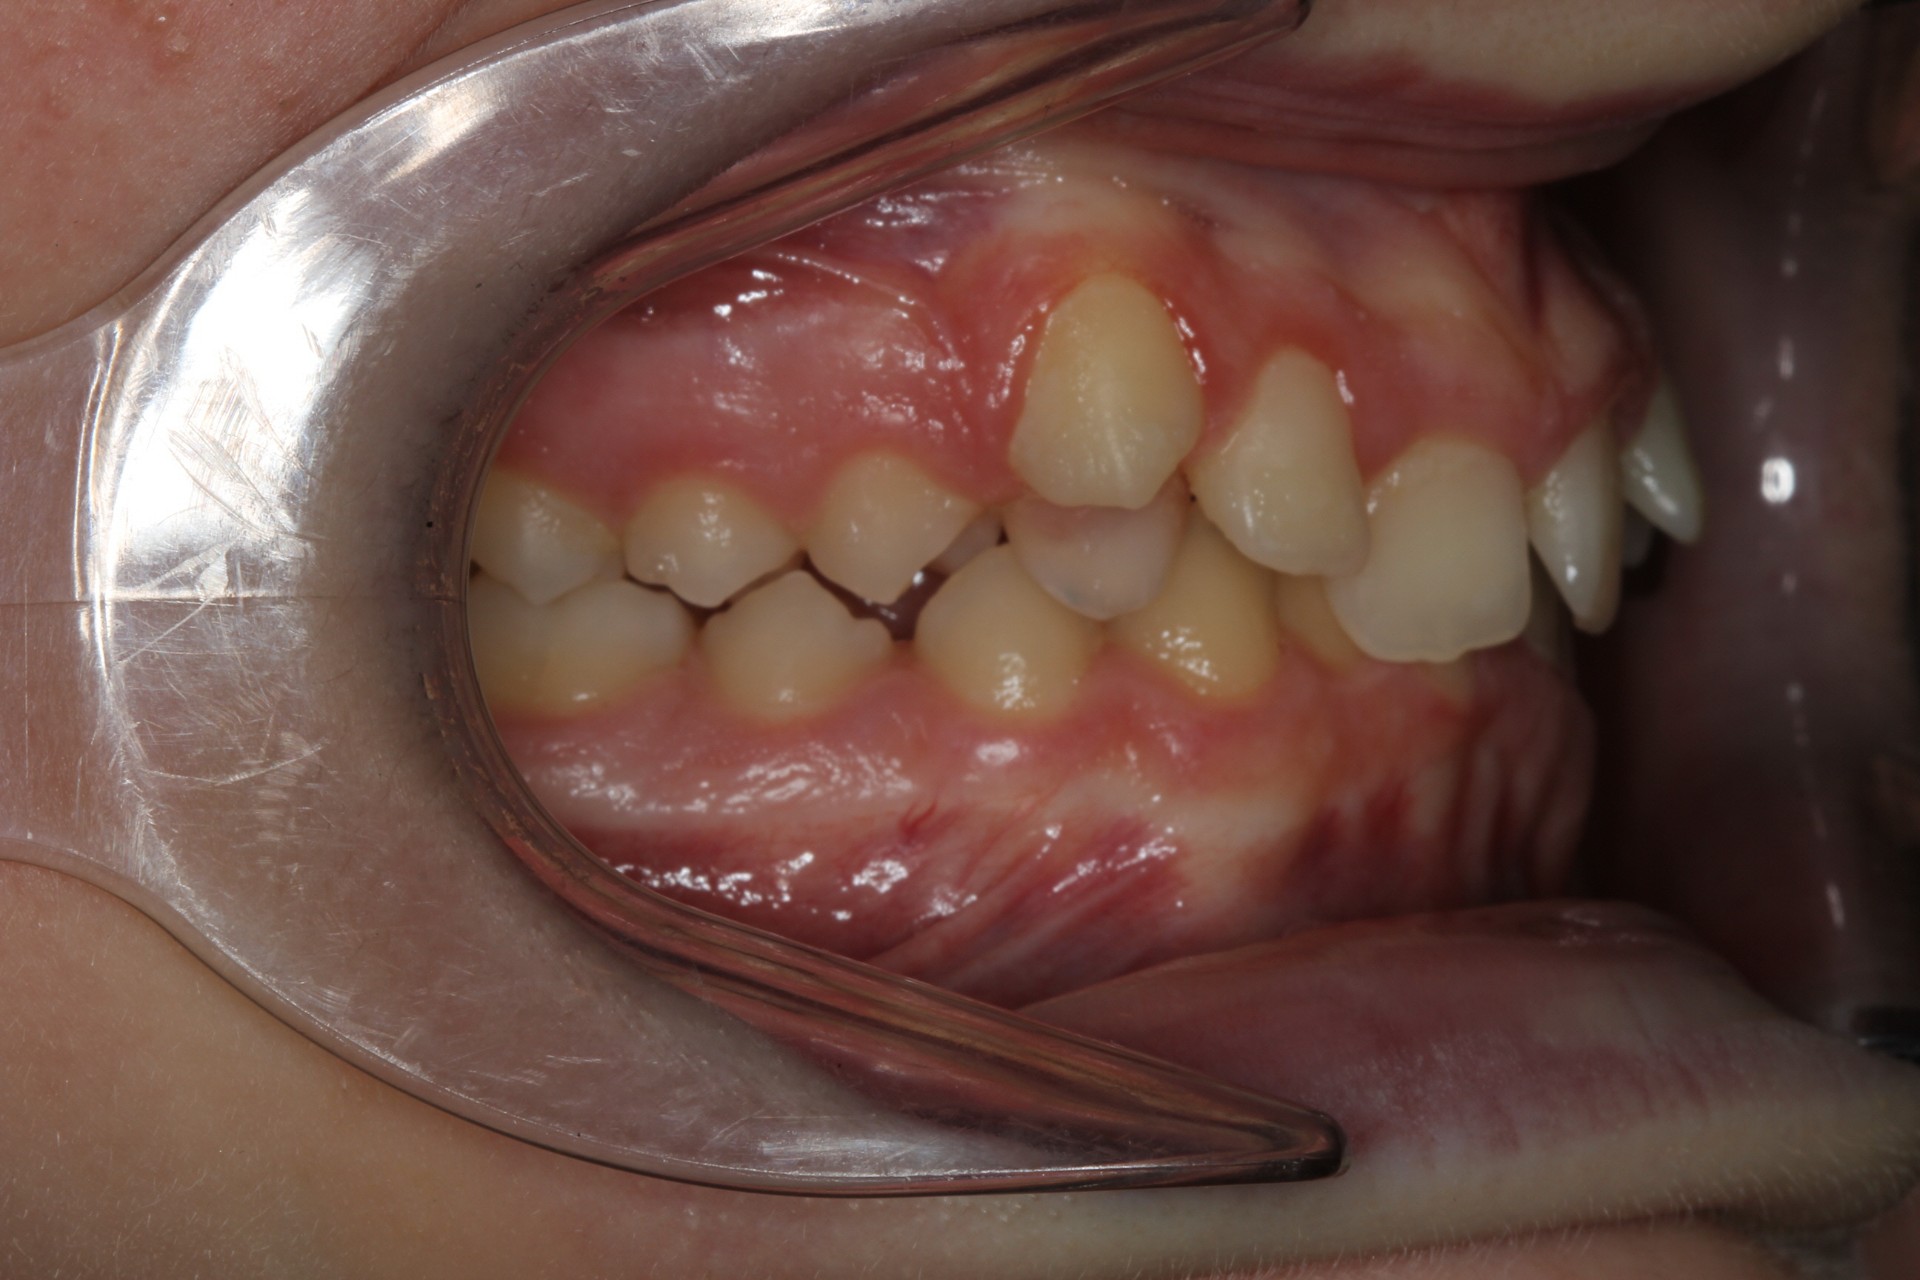

Crowding – Child case